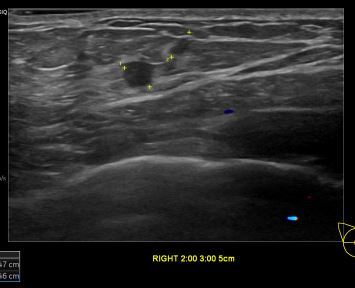

상기환자는 우측유방 만져지는 멍우리와 조직검사 권유받고  내원하신 40대 초반 여성분으로 의심스러운 우측 혹 조직검사 시행해 유방암 진단되었습니다.